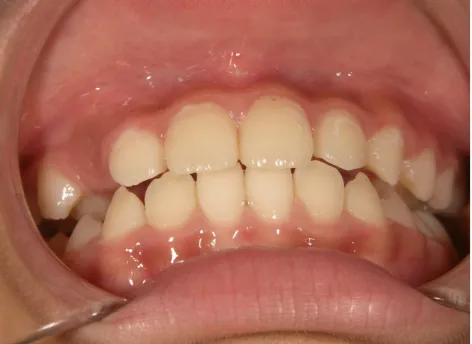

治療中➁小3:9y8m QH、BH、前歯並び替え終了

モノブロック装置(筋機能的咬合誘導装置)スタート